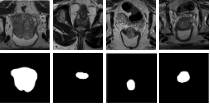

Prostate segmentation from magnetic resonance imaging (MRI) is a challenging task. In recent years, several network architectures have been proposed to automate this process and alleviate the burden of manual annotation. Although the performance of these models has achieved promising results, there is still room for improvement before these models can be used safely and effectively in clinical practice. One of the major challenges in prostate MR image segmentation is the presence of class imbalance in the image labels where the background pixels dominate over the prostate. In the present work we propose a DL-based pipeline for cropping the region around the prostate from MRI images to produce a more balanced distribution of the foreground pixels (prostate) and the background pixels and improve segmentation accuracy. The effect of DL-cropping for improving the segmentation performance compared to standard center-cropping is assessed using five popular DL networks for prostate segmentation, namely U-net, U-net+, Res Unet++, Bridge U-net and Dense U-net. The proposed smart-cropping outperformed the standard center cropping in terms of segmentation accuracy for all the evaluated prostate segmentation networks. In terms of Dice score, the highest improvement was achieved for the U-net+ and ResU-net++ architectures corresponding to 8.9% and 8%, respectively.